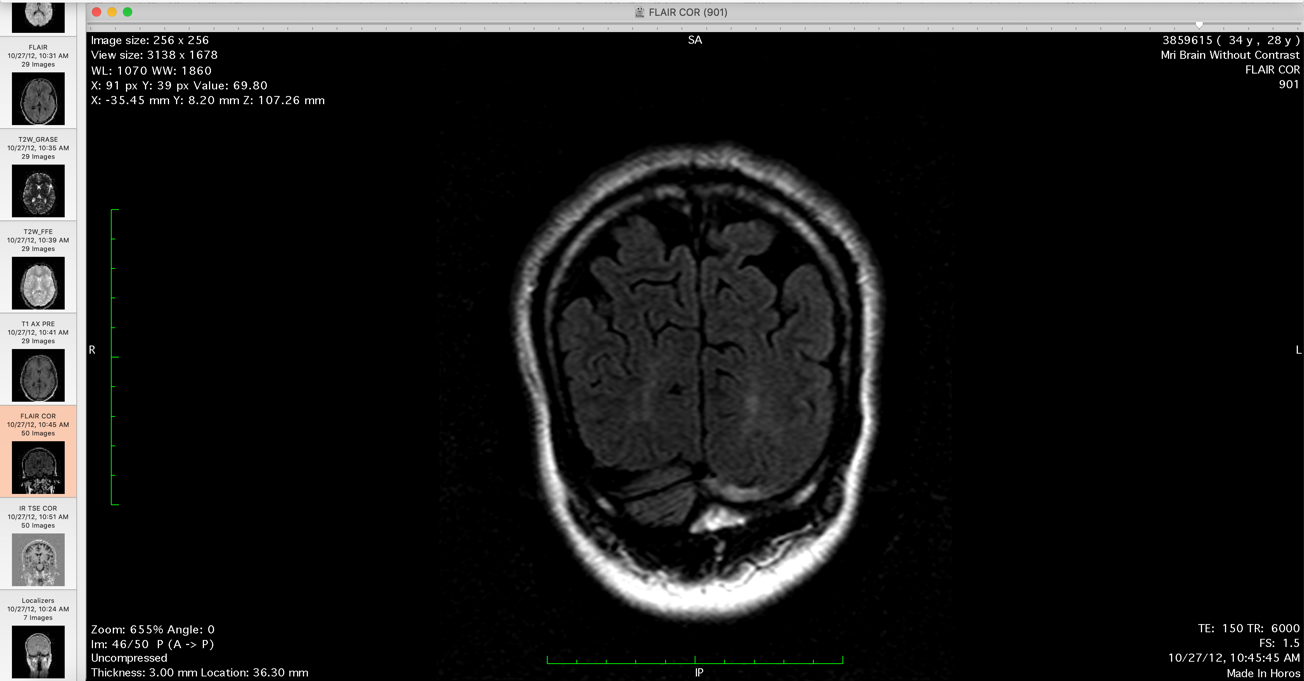

Pia: So you have MRI scans with you?

Me: Yup I have the MRI scans with me.

Me: There is a usually a massive headache there are lesions in the upper cervical column at that point and that would create both the headaches and then nausea vomiting and then there are peripheral pains which can become excruciating. Its almost unbearable at that point so. I have some of the MRI examples, there are actually quiet a few.

So that shows posterior brain [lesions], and you can see.... Its mostly the occipital region. And what typically happens is that.... if

Pia: So where is the lesion?

[these are the clear lesions shown to Dr. Pia, which he deludedly professes not to be able to see its clinical fraud in statement]

Me: Keep going back. So there you go, these intensities here.

Pia: Lets look at the transversal slides.

Me: Its depends on the, what I did is that I had the radiologist do a comparison of the different MRIs and then he noted where these intensities.

He compared 4 brain MRIs in this series. He compared the MRI with the 2012 MRI and then 2017. So he is basically comparing 4 MRIs the 20 and.... last year January that are no intensities in the occipital lobes as there are in the 2012 or in the 2....

Me: Otherwise there is change in the occipital lobe after the 2010. So these two MRI series here they both have signal intensity changes in the posterior part of my brain.